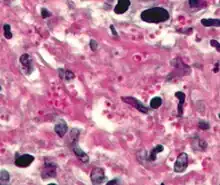

Haematoxylin and eosin (H&E)

Haematoxylin and eosin staining is frequently used in histology to examine thin tissue sections.[10] Haematoxylin stains cell nuclei blue, while eosin stains cytoplasm, connective tissue and other extracellular substances pink or red.[10] Eosin is strongly absorbed by red blood cells, colouring them bright red. In a skillfully made H&E preparation the red blood cells are almost orange, and collagen and cytoplasm (especially muscle) acquire different shades of pink.